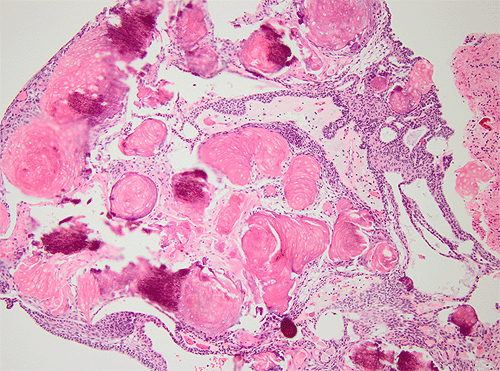

Craniopharyngioma, HE: Low and high magnification of an adamantinomatous type of cranipharyngioma. Note the presence of microscyst formation, wet keratin pearls (arrow) and the stellate cells around the keratin pearls.